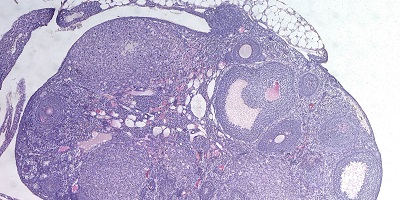

En un enorme esfuerzo, 300 científicos de todo el mundo han estudiado el genoma de más de medio millón de mujeres conservado en varias bases de datos. Buscaban variaciones en el ADN que estuvieran relacionadas con la aparición temprana o tardía de la menopausia. El trabajo, publicado este miércoles en la revista Nature, ha encontrado al menos 290 variantes en aquellas féminas con un fin de la vida reproductiva que se alejaba de la edad media, ya fuera por exceso o por defecto. La cifra supone multiplicar por cinco las modificaciones genéticas que se sabía afectaban a la fertilidad natural.

Además del incremento de variaciones genéticas conocidas que afectan a la menopausia, este trabajo ha destacado la conexión entre esta senescencia ovárica y los mecanismos que regulan la reparación del ADN de las células o la propia muerte celular, la llamada apoptosis, cuando las células se suicidan si algo va mal. Lo explica Roig: “La gran mayoría de los genes que identificamos de estos 290 están involucrados en la reparación del ADN dañado”. En otros tejidos y partes del cuerpo humano, lo que hacen es corregir errores o fallos a nivel genético provocados factores internos o ambientales. “Nosotros encontramos genes de reparación del ADN relacionados con la aparición de la menopausia que funcionan de varias maneras diferentes: desde la etapa de replicación del ADN cuando se genera la reserva de óvulos en el feto, hasta la reparación de roturas en el ADN que se hacen para introducir variabilidad genética en los óvulos durante un proceso llamado meiosis, también en etapas fetales”, detalla Roig.

Pero además hay una concentración de variaciones en una cincuentena de genes que intervienen en la muerte celular. “Cuando una célula sufre daño en su ADN, la maquinaria de reparación del ADN activa mecanismos de bloqueo de la progresión del ciclo celular para dar tiempo a la célula a reparar el daño. Si esto no puede darse, se activan mecanismos de apoptosis con tal de eliminar esta célula dañada y evitar problemas para el organismo. Del mismo modo, estos procesos también ocurren en los óvulos”, comenta Roig.